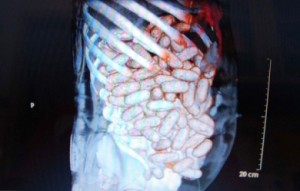

Saisie de drogue dure à l’aéroport de Bamako-Sénou : 1,200 kg de cocaïne découvert dans le ventre d’un Nigérian

Publié le 1st October 2013

C’est donc une grosse prise effectuée le vendredi 27 septembre dernier par la brigade anti-stupéfiant de l’aéroport de Bamako-Senou. En effet, un Nigérian répondant au ... Lire

Plus d’un kilogramme de cocaïne saisi a l’aéroport de Bamako Sénou

Publié le 30th September 2013

La cellule aéroportuaire anti-trafic de drogue, dirigée par le Capitaine Alhader Yoro Maiga, vient de réussir un coup de maitre. Le vendredi 27 septembre 2013, ... Lire